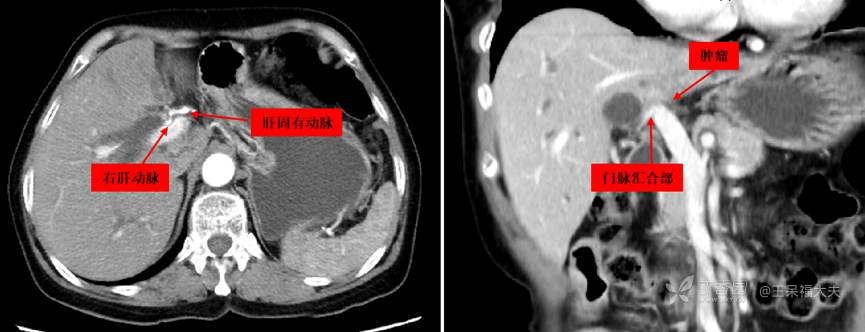

患者72岁女性,无明显诱因下出现皮肤巩膜黄染3周,当地检查提示“肝门部胆管癌”1周入院。既往体健,查体除皮肤巩膜重黄染无特殊。影像检查提示肝内外胆管扩张,门脉左支闭塞,右肝动脉根部受侵,如图:

图2:右肝动脉根部可疑受侵;门脉左支闭塞,浸润至左右门脉汇合部。